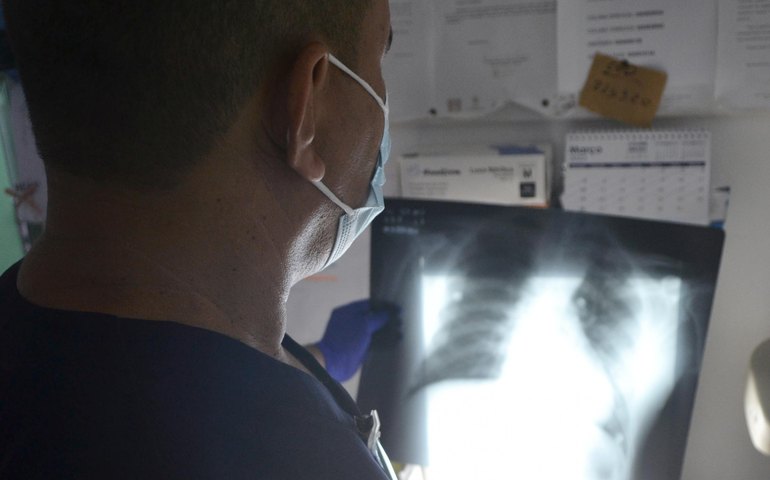

Dia Mundial de Combate à Tuberculose: doença pode atingir outros órgãos além do pulmão

No dia 24 de março é comemorado o Dia Mundial de Combate à Tuberculose. O Hospital Escola Helvio Auto (HEHA), unidade assistencial da Universidade Estadual de Ciências da Saúde de Alagoas (Uncisal), atende e fornece tratamento a pacientes com tuberculose como doença oportunista ao HIV/AIDS e ainda casos de tuberculose extrapulmonar.

Infectologistas alertam para a necessidade de atenção na conclusão do diagnóstico de tuberculose extrapulmonar, uma vez que os sintomas podem ser facilmente confundidos com os de outras doenças. A tuberculose pulmonar é o tipo mais corriqueiro, mas a enfermidade também pode atingir outros órgãos e sistemas do corpo e seu diagnóstico diferencial pode ser difícil para alguns pacientes. As infecções de tuberculose extrapulmonar mais comuns são da pleura, linfonodos, sistema nervoso central, rins, fígado, pele, ossos e olhos.

Em casos específicos de tuberculose extrapulmonar do sistema nervoso central e óssea, o tratamento se prolonga até um ano. Em 2021, o Hospital Escola Dr. Helvio Auto tratou 277 casos de tuberculose pulmonar; já em 2022 houve uma discreta diminuição, contabilizando 274 pacientes. Em relação à tuberculose extrapulmonar, o HEHA atendeu 43 casos em 2022; já nos dois primeiros meses deste ano foram registrados 15 casos. Ainda há pacientes que desenvolvem as duas formas da doença concomitantemente. “O diagnóstico diferencial da tuberculose extrapulmonar é muito vasto e pode ser muito difícil de ser feito. É necessário que o paciente seja visto com atenção, uma vez que requer uma boa análise da história clínica para que sejam solicitados os exames corretos”, diz o médico.